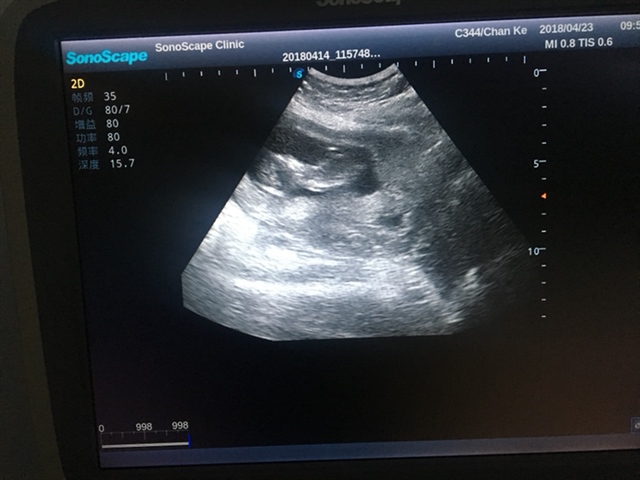

产前检查 唐氏筛查